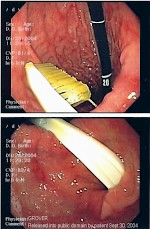

Abb.1 - Endoskopische Entfernung einer verschluckten Zahnbürste - Foto: Wikipedia